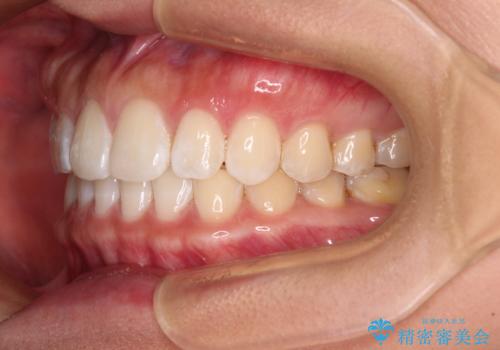

【モニター】前歯のすきっ歯をインビザラインで改善

- 上顎前歯の隙間と口元の突出感を気にして来院された患者様です。

高校生の時に行った矯正治療の後戻りであり、歯列不正は軽度であったので、インビザラインにて治療を行うこととしました。

すきっ歯はあっという間に後戻りを起こすので、可及的に後戻りを防止するために、上下前歯部を舌側からワイヤーで固定しています。

通常は下顎前歯のみに行っていますが、空隙歯列弓では上顎でも行っています。